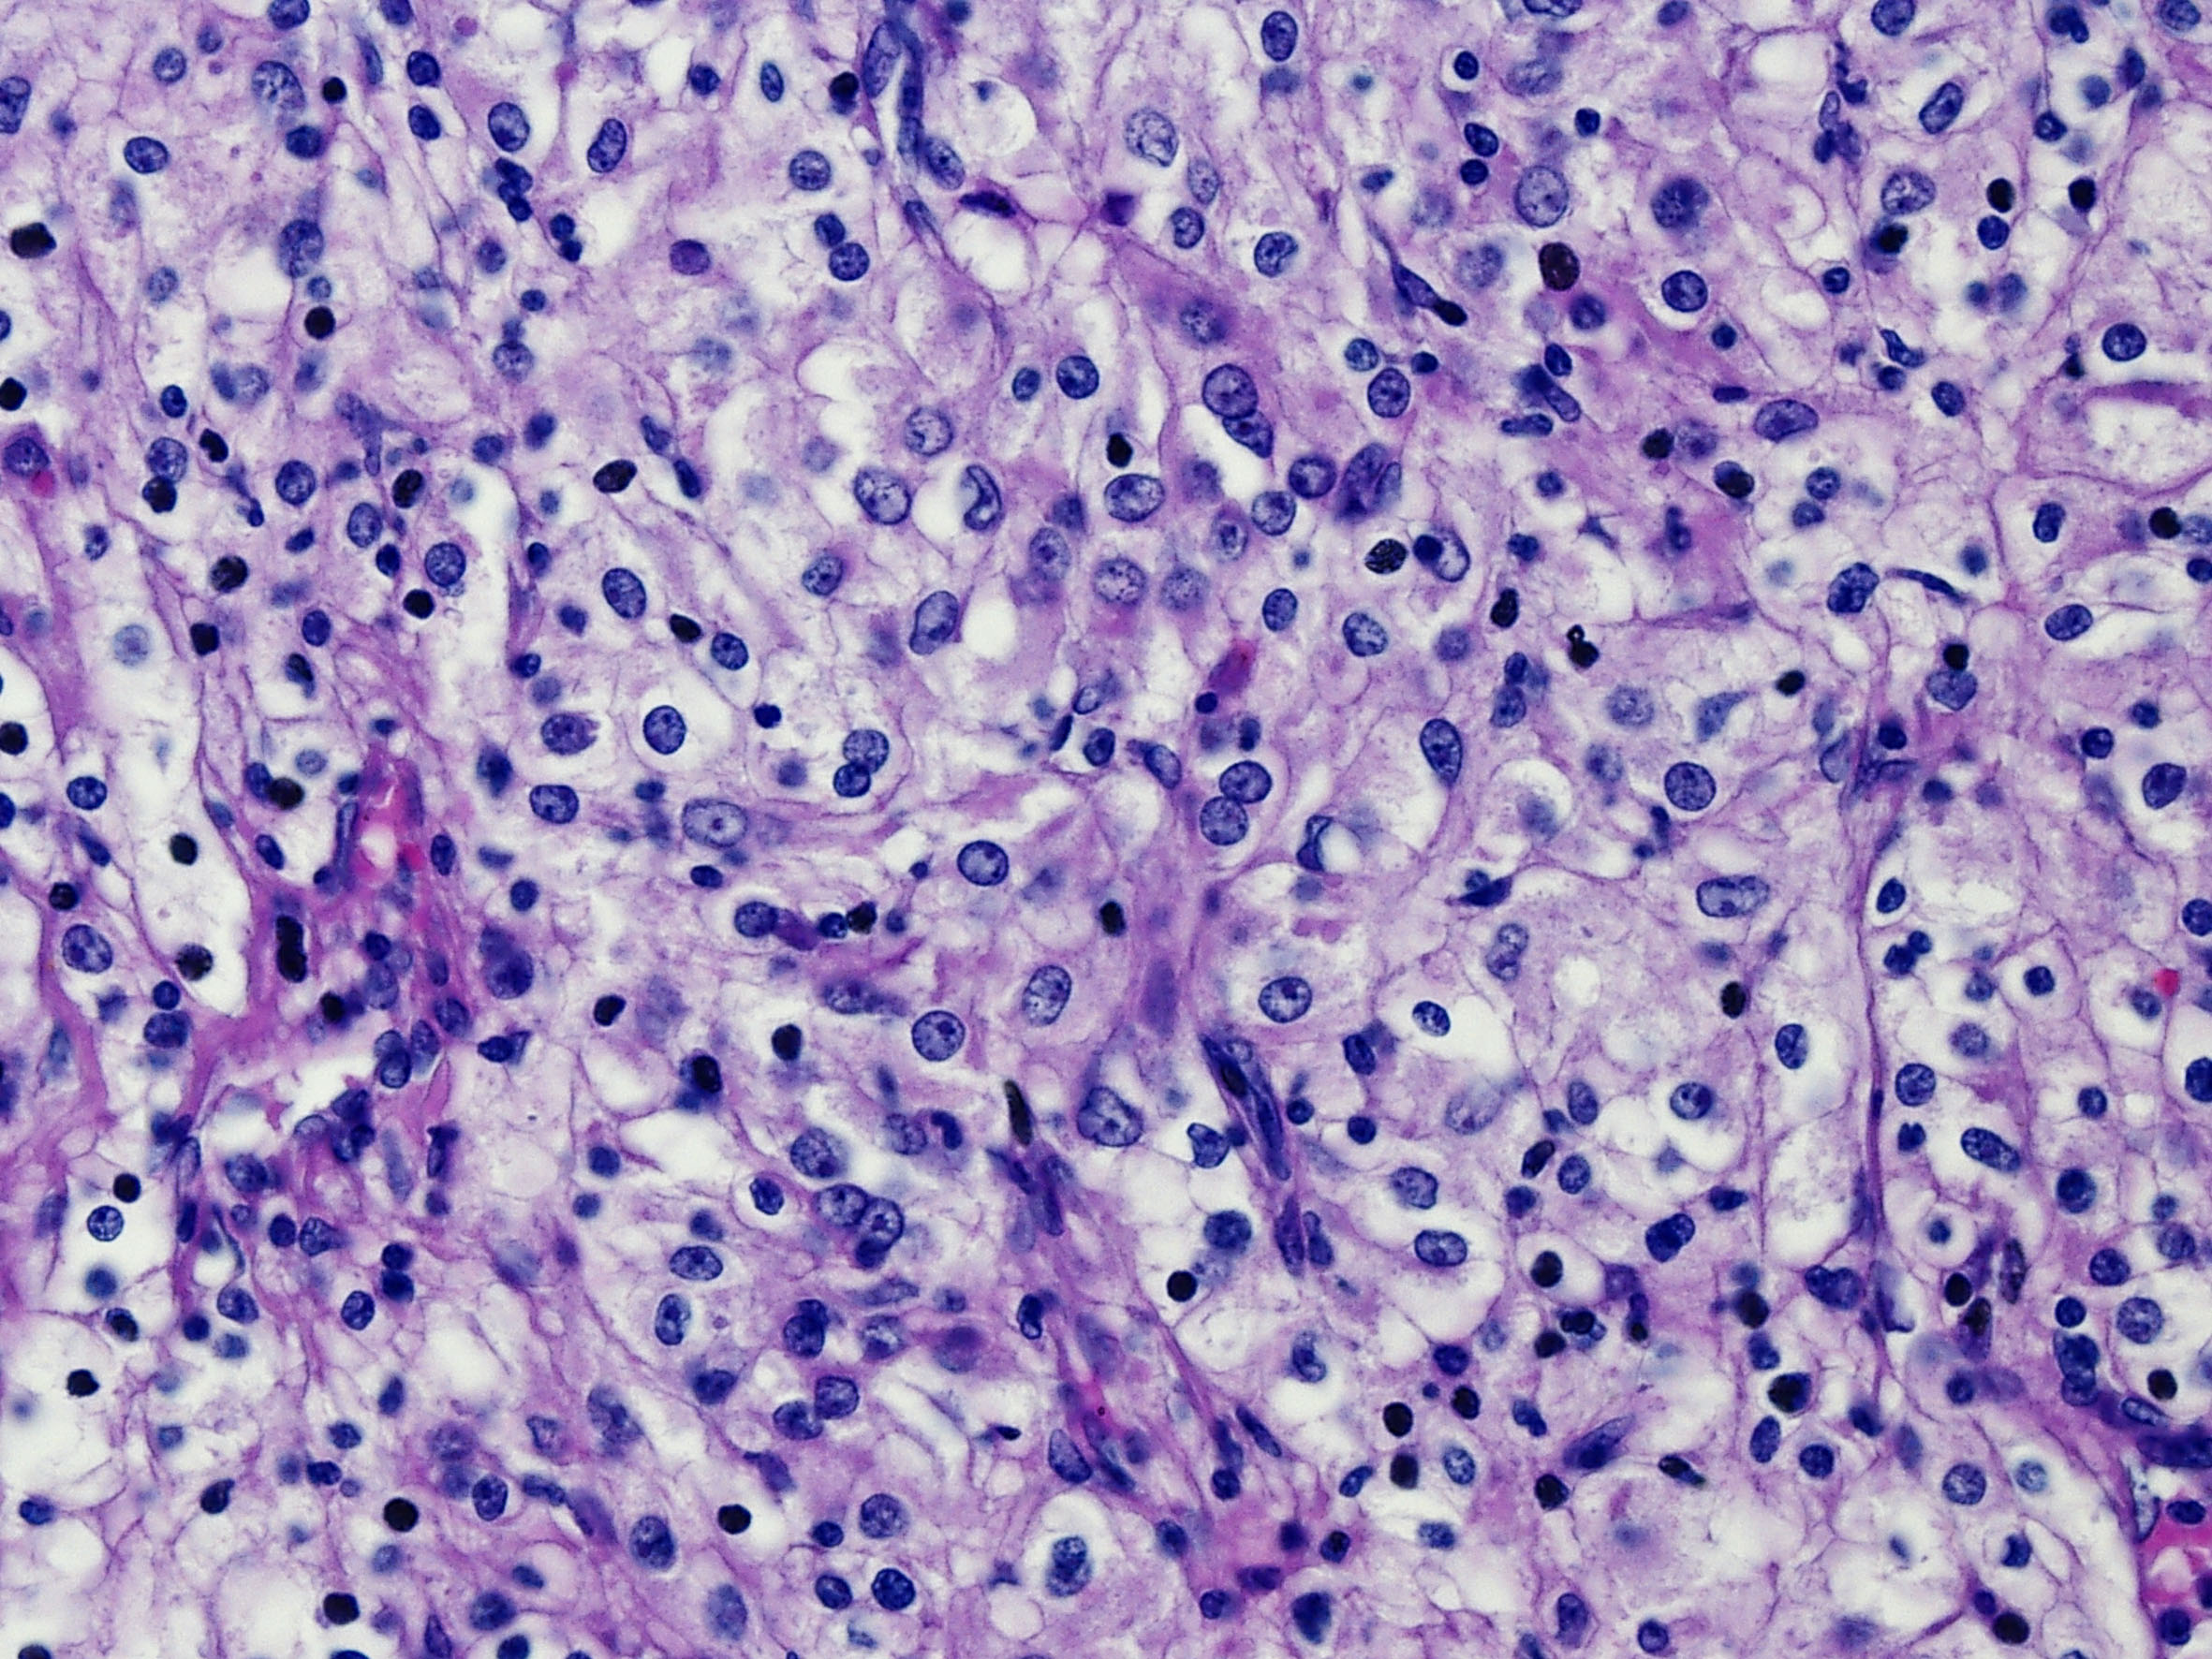

Classification of renal tumors

Case ID: 59